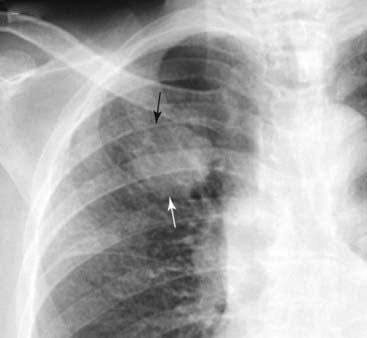

Figure 3-2 Right lower lobe pneumonia.

An area of increased opacification is in the right midlung field (solid black arrow) that has indistinct margins (solid white arrow) characteristic of airspace disease. The minor fissure (dotted black arrow) appears to bisect the disease, locating this pneumonia in the superior segment of the right lower lobe. The right heart border and the right hemidiaphragm are still visible because the disease is not in anatomical contact with either of those structures.